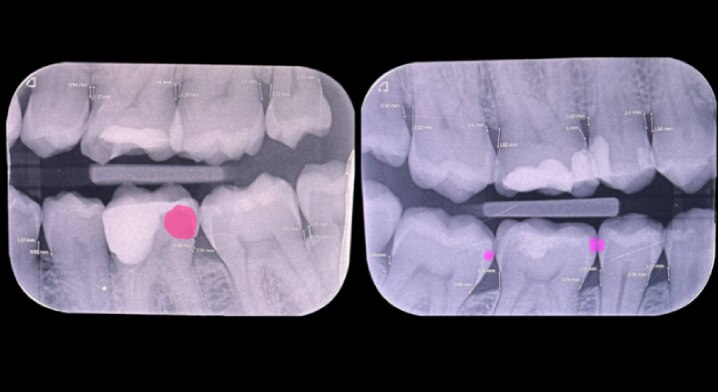

Abb. 6 und 7: Bitewing-Aufnahmen aus dem Jahr 2024 belegen keinen signifikanten röntgenologischen Attachmentverlust.

Bitewing-Aufnahmen aus dem Jahr 2024 belegen keinen signifikanten röntgenologischen Attachmentverlust.

Der Patient berichtete über unangenehmen Geschmack im Mund, häufiges Zahnfleischbluten sowie Dentinhypersensibilität. Chlorhexidinprodukte wurden aufgrund von Nebenwirkungen nicht vertragen. Radiologisch zeigte sich kein signifikanter Knochenabbau, klinisch jedoch beginnender Attachmentverlust unter Anderem regio 26 (Abb. 5 bis 7).